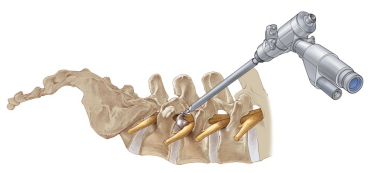

經皮椎間孔鏡技術微創治療腰椎間盤突出癥

經皮椎間孔鏡椎間盤切除術(percutaneous transforaminal endoscopic discectomy,PTED)是治療腰椎間盤突出癥的一項新的微創技術。與傳統開放式椎間盤切除術相比,擁有創傷小、出血少、術后康復快、疤痕小等優點。

椎間孔鏡構造類似于關節鏡,手術全程采用影像定位、高清視頻監控,將復雜的操作簡單化,將危險的手術安全化。猶如腹腔鏡摘除膽囊一樣,小切口高、精、準完成大手術。是目前治療腰椎間盤突出癥最先進、最微創、切口最小、效果最好、恢復最快、最經濟的手術。